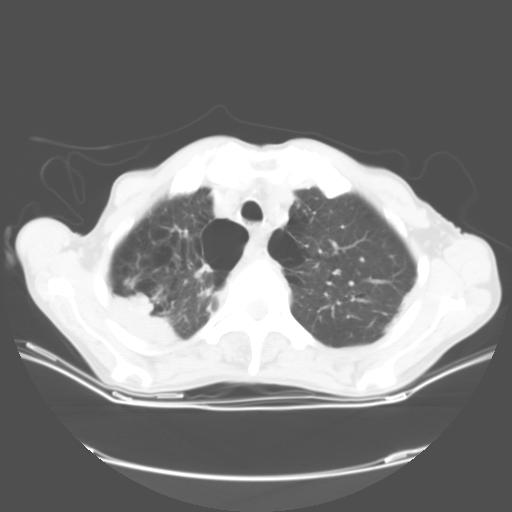

女,72岁,咳嗽一周余,突发右下肢无力二天。

来院做头颅+胸部ct平扫

胸部病变平扫35hu,增强强化至70hu

这个病人首先是胸部病变的定位到底是肺内还是肺外。仔细观察块影位于胸膜下,与胸膜间有透亮带,且近端血管未见明显推移而是引流样改变,形态分叶,说明这个病灶位于肺内胸膜下。很可能是腺癌,腺癌最易致颅内高密度转移灶。局部胸膜有侵犯。

本例颅内见多发大小不等高密度灶,有强化及水肿;另外,胸锁关节层面可能是第四胸椎及右侧肋骨起始部骨质欠连续,椎旁软组织肿胀,建议调骨窗观察。

诊断:右下肺癌伴颅内、胸椎、肋骨转移可能性最大。